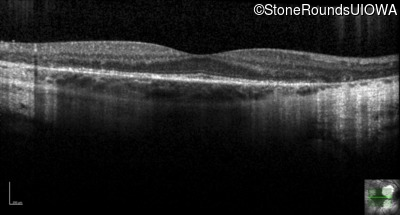

Optical Coherence Tomography - Right - 20/16

Exemplar / OCT Stack